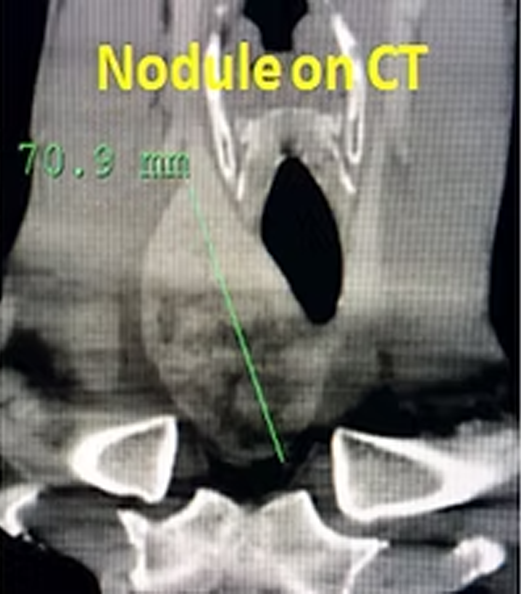

Percutaneous ablation is the preferred nonsurgical treatment in most thyroid nodules. However, sometimes the nodule(s) may be too large (>6cm) or too many (>4-5) or they may extend into the chest (plonging goiter). In such situations, percutaneous ablation may be difficult, less effective or impractical while embolization may become an attractive alternative. In embolization, the feeding vessels of the nodule(s) are occluded with a simple angiography procedure. After the treatment, the nodule(s) shrink significantly and the complaints as well as cosmetic appearance improve markedly.